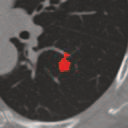

Deep learning based medical image segmentation models usually require large datasets with high-quality dense segmentations to train, which are very time-consuming and expensive to prepare. One way to tackle this challenge is by using the mixed-supervised learning framework, in which only a part of data is densely annotated with segmentation label and the rest is weakly labeled with bounding boxes. The model is trained jointly in a multi-task learning setting. In this paper, we propose Mixed-Supervised Dual-Network (MSDN), a novel architecture which consists of two separate networks for the detection and segmentation tasks respectively, and a series of connection modules between the layers of the two networks. These connection modules are used to transfer useful information from the auxiliary detection task to help the segmentation task. We propose to use a recent technique called "Squeeze and Excitation" in the connection module to boost the transfer. We conduct experiments on two medical image segmentation datasets. The proposed MSDN model outperforms multiple baselines.